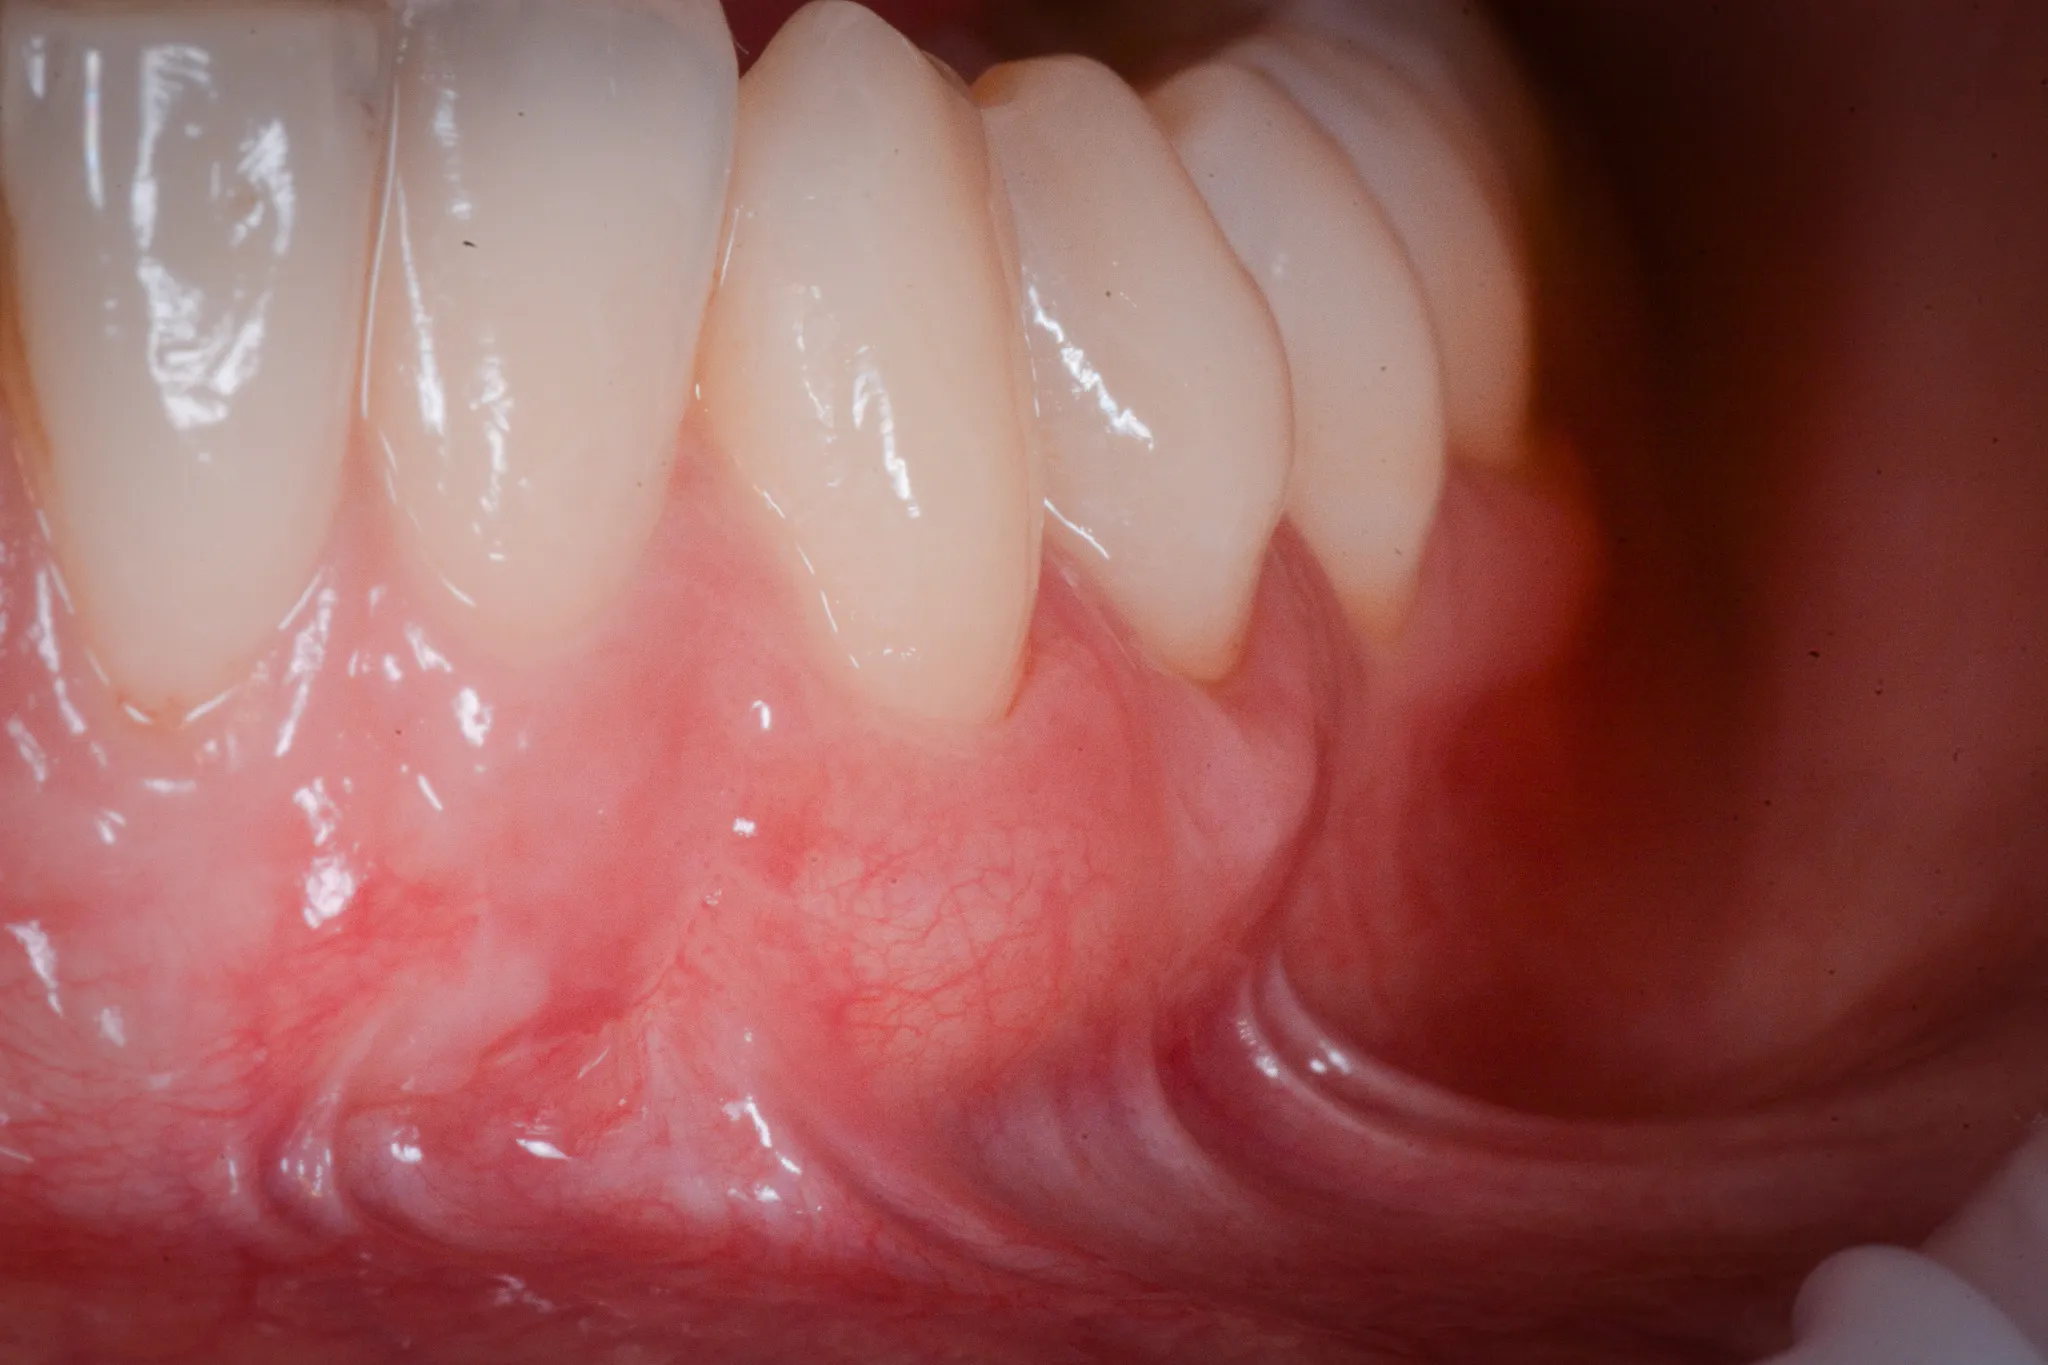

Il tessuto gengivale vero è un tessuto connettivo rivestito da epitelio cheratinizzato (in sostanza, un tessuto più spesso e resistente adeso all’osso sottostante). Quando si ritira, espone la radice del dente — una superficie che non è progettata per stare a contatto con l’ambiente orale. La radice è più porosa dello smalto, più vulnerabile alla carie, più sensibile agli stimoli termici.

Inoltre, a volte la gengiva si assottiglia per vari motivi lasciando spazio da un tessuto più delicato (mucosa orale) che è identico a quello che riveste le guancie e l’interno delle labbra.

Biotipo sottile. Alcune persone hanno gengive sottili per costituzione — una banda stretta di cheratinizzata, un periostio esile, una corticale ossea vestibolare ridotta a un velo. In questi pazienti, anche stimoli minimi possono innescare la recessione.

Malposizione dentale. Un dente vestibolarizzato, fuori dall’arco, ha meno osso e meno gengiva dalla parte esterna. La recessione è quasi inevitabile.

Il dente che “sembra più lungo” è il segno visivo. Il paziente lo nota allo specchio, oppure lo nota il dentista durante un controllo.

L’altro criterio molto importante è l’ampiezza del tessuto gengivale. Sotto i due millimetri, è consigliabile intervenire.